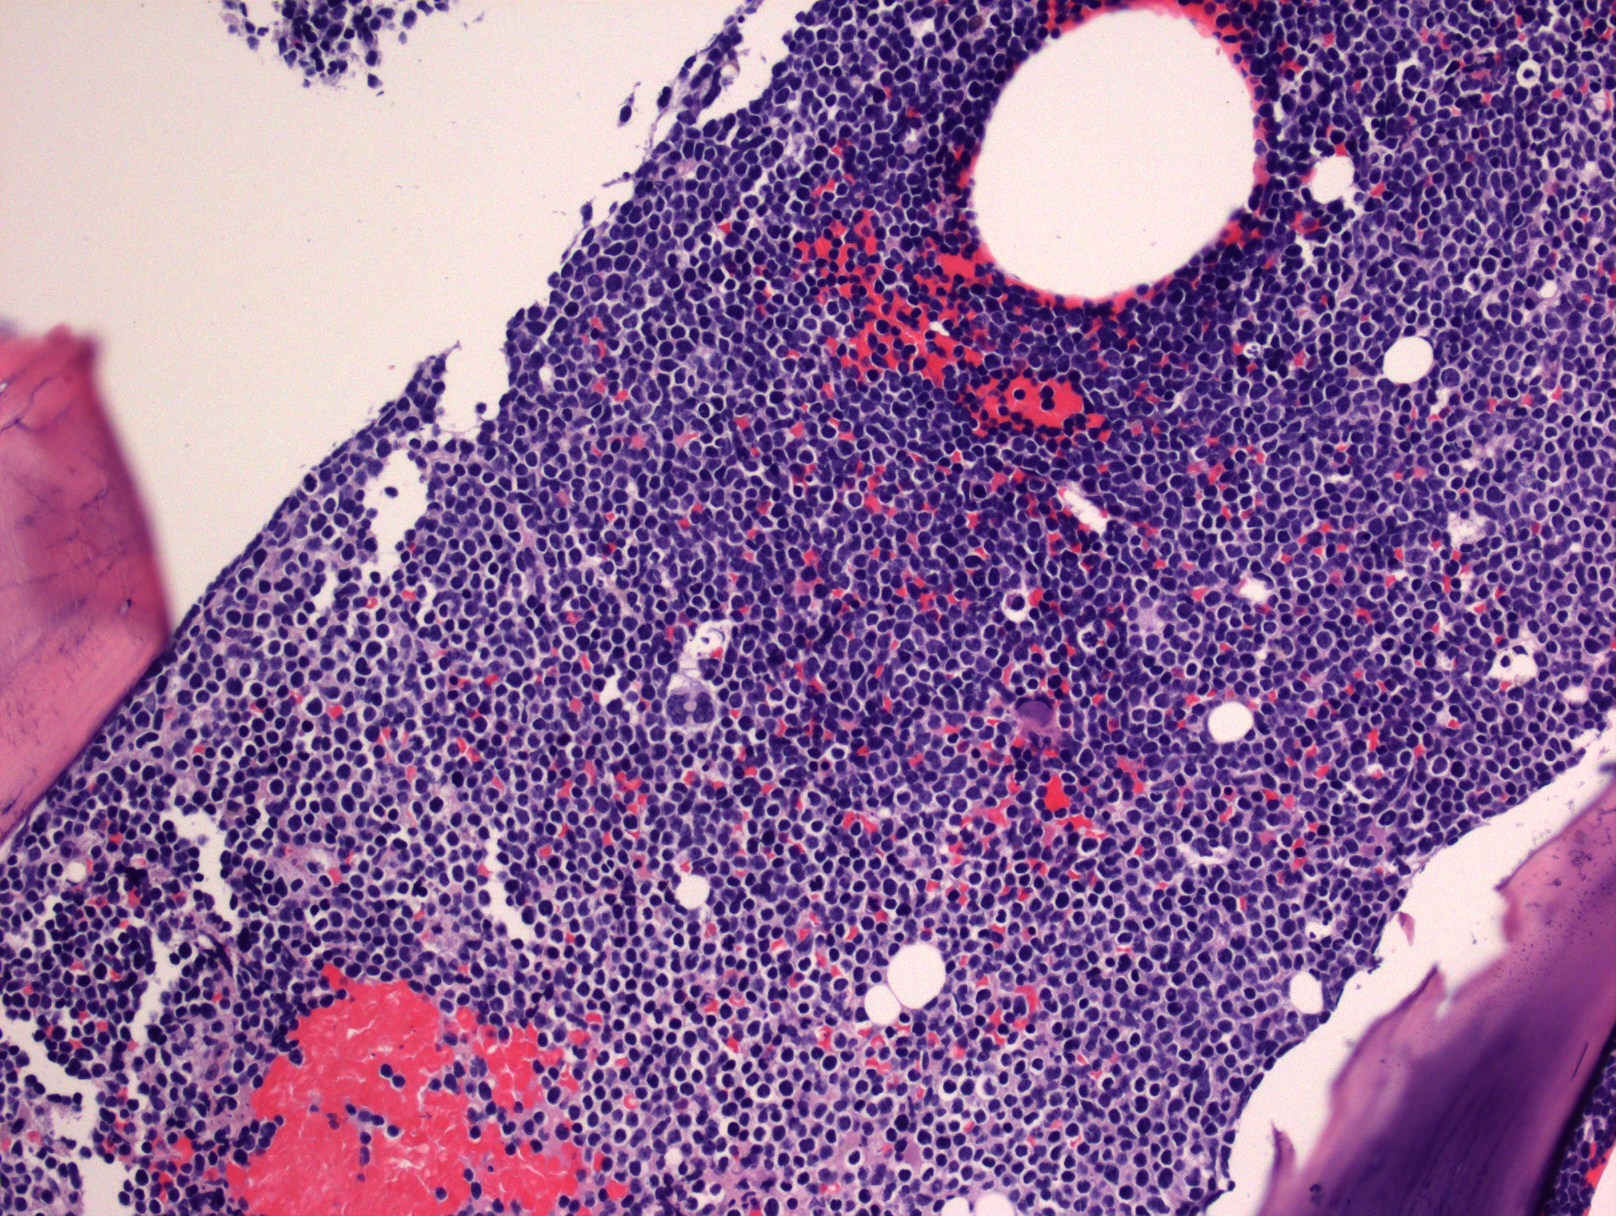

- 在骨髓和外周血涂片中,肿瘤细胞形态与 B-ALL 类似,二者无法区分。肿瘤细胞中等大小伴高 N/C,但细胞大小可异差别较大,染色质可以从致密到疏松,有的病例甚至类似成熟淋巴细胞。

- 在骨髓活检样本,T-ALL 虽累及骨髓,但常不像 B-ALL 那样弥漫取代造血成分。

- 髓外受累的部位病变通常呈弥漫性分布,偶尔也可出现部分淋巴结受累,核分裂像多,可见灶性“星空”现象。